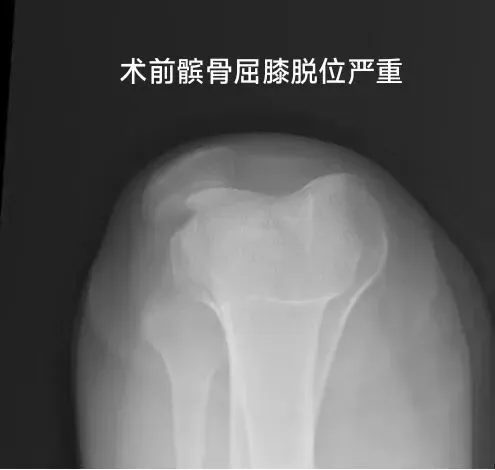

复杂病情 求医无门

此次接受手术的患者是一名20岁年轻女性,多年来饱受膝关节反复脱位、不稳的折磨,日常生活和运动能力受到严重影响。此前,她辗转多家医院,均未得到有效治疗。到长治市第二人民医院运动医学科就诊后,经详细检查,被确诊为“重度习惯性髌骨脱位”。该病症病情复杂,髌骨轨道严重异常,股骨滑车发育不良,相关软组织平衡失调,属于运动医学领域极具挑战性的手术病例。